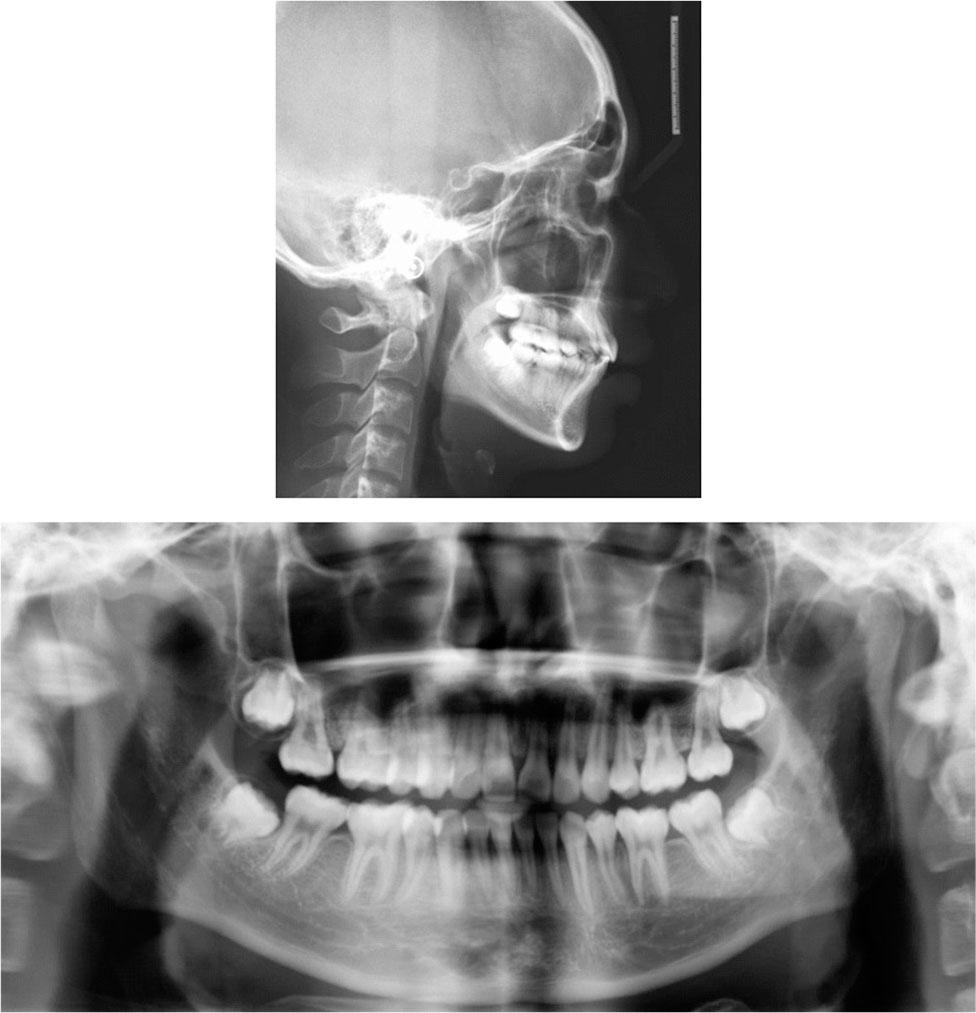

Cephalometric measurements (T1 Pretreatment; T2 12 months after Twin-block treatment; T3 36 months after fixed orthodontic treatment)

| Measurement | Norm | T1 | T2 | T3 |

|---|---|---|---|---|

| SNA(°) | 83.0 | 87.3 | 86.8 | 86.1 |

| SNB(°) | 80.0 | 77.9 | 79.6 | 81.6 |

| ANB(°) | 3.0 | 9.4 | 7.2 | 4.5 |

| NP-FH(°) | 85.0 | 81.5 | 84.5 | 84.4 |

| NA-PA(°) | 6.0 | 19.8 | 16.5 | 10.0 |

| U1-SN(°) | 105.0 | 108.8 | 101.3 | 107.9 |

| U1-NA(°) | 22.0 | 21.6 | 14.5 | 21.9 |

| L1-NB(°) | 30.0 | 37.3 | 41.4 | 25.6 |

| IMPA(°) | 88.0 | 111.0 | 113.2 | 98.7 |

| FMIA(°) | 67.0 | 44.0 | 43.1 | 59.0 |

| FMA(°) | 25.0 | 25.0 | 23.7 | 22.3 |

| Y-axis angle (°) | 65.8 | 65.8 | 64.2 | 64.0 |

| Z-angle(°) | 75.0 | 52.8 | 59.7 | 65.3 |

| Po-Go(mm) | – | 6.9 | 7.2 | 7.3 |

| Gn-Co(mm) | – | 10.2 | 10.8 | 11.1 |